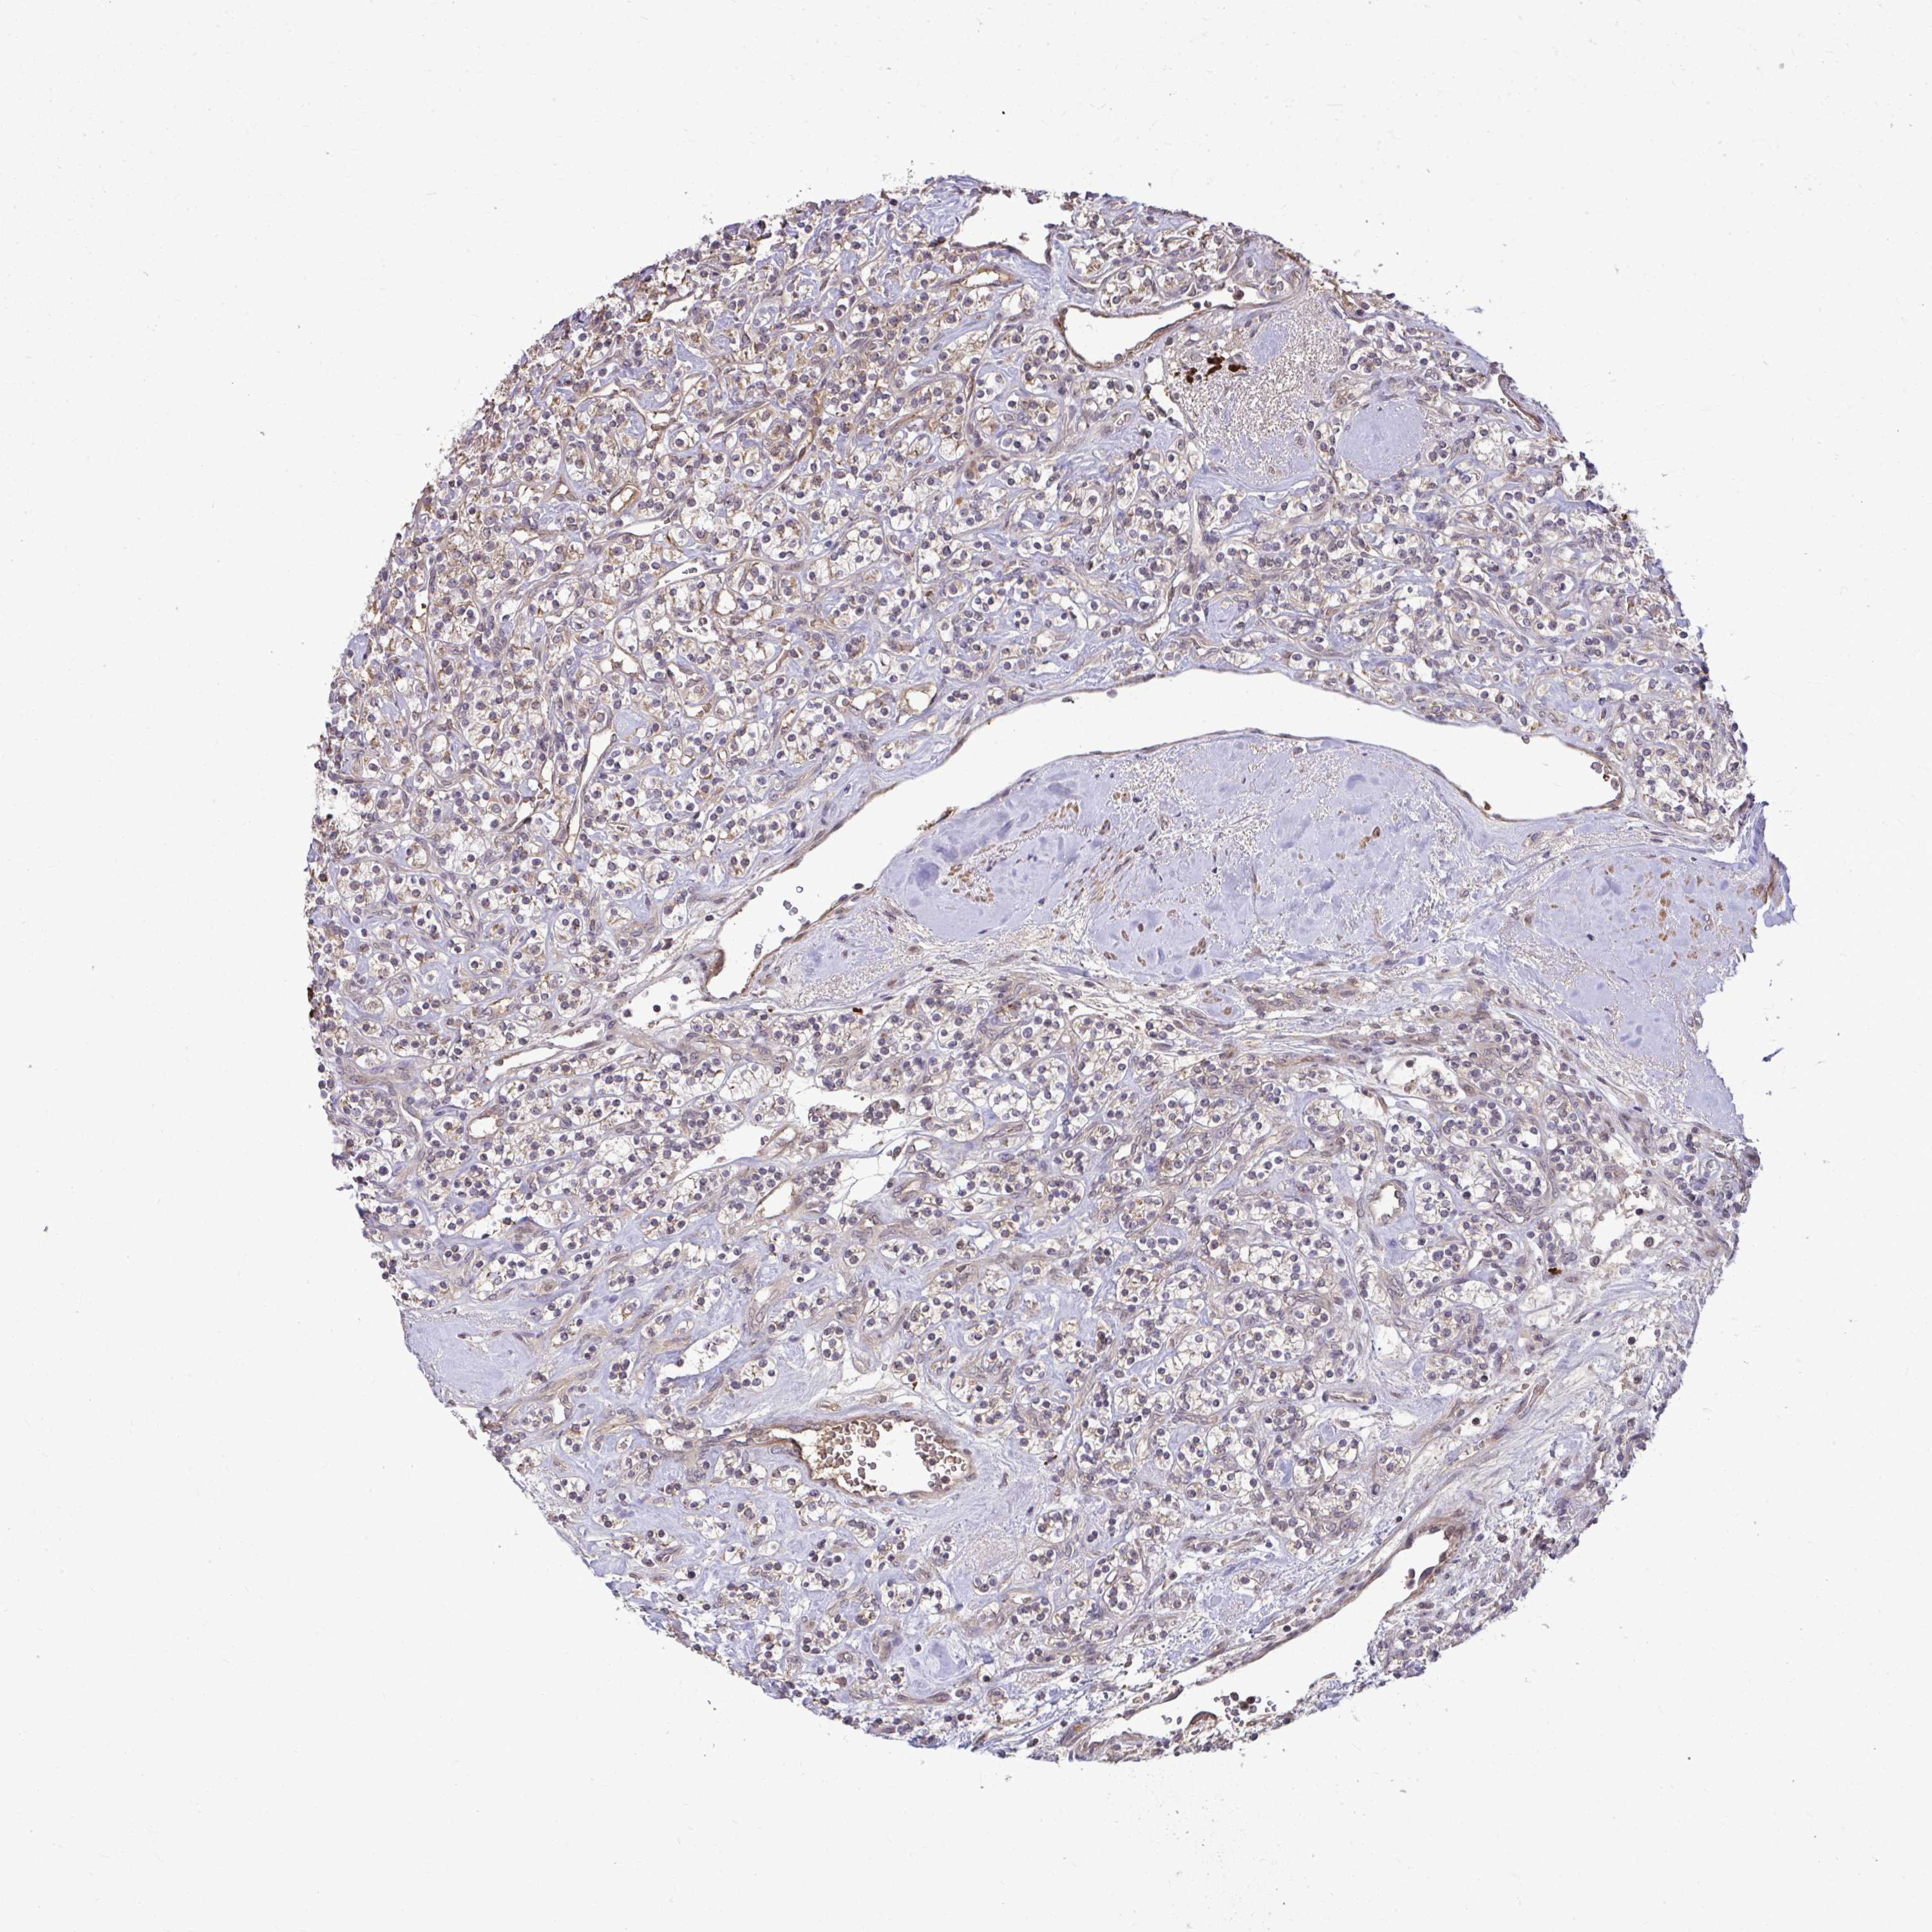

KIDNEY RENAL CLEAR CELL CARCINOMA (VALIDATION) - Interactive survival scatter ploti

The Survival Scatter plot shows the clinical status (i.e. dead or alive) for all individuals in the patient cohort, based on the same data that underlies the corresponding Kaplan-Meier plots. Patients that are alive at last time for follow-up are shown in blue and patients who have died during the study are shown in red.

The x-axis shows the expression levels (FPKM) of the investigated gene in the tumor tissue at the time of diagnosis. The y-axis shows the follow-up time after diagnosis (years). Both axes are complimented with kernel density curves demonstrating the data density over the axes. The top density plot shows the expression levels (FPKM) distribution among dead (red) and alive patients (blue). The right density plot shows the data density of the survived years of dead patients with high and low expression levels respectively, stratified using the cutoff indicated by the vertical dashed line through the Survival Scatter plot. This cutoff is automatically defined based on the FPKM cutoff that minimizes the p-score. The cutoff can be changed by dragging the vertical line or by entering a cutoff value in the square labeled "Current cut-off".

Under the Survival Scatter plot the p-score landscape (black curve; left axis) is shown together with dead median separation (red curve; right axis). Dead median separation is the difference in median mRNA expression between patients who have died with high and low expression, respectively. It is calculated as follows: median FPKM expression of dead patients with high expression - median FPKM expression of dead patients with low expression. This is intended to aid the user in visually exploring custom cutoffs and the associated p-scores and dead median separation.

Individual patient data is displayed and can be filtered by clicking on one or more of the category buttons on the top of the page. Categories describing expression level and patient information include: high, low, alive, dead, female, male and tumor stages. The scale of the x-axis can be toggled between linear and log-scale by clicking on the "x log" button. Mouse-over function shows TCGA ID, patient information and mRNA expression (FPKM) for each patient.

& Survival analysisi

Kaplan-Meier plots summarize results from analysis of correlation between mRNA expression level and patient survival. Patients were divided based on level of expression into one of the two groups "low" (under cut off) or "high" (over cut off). X-axis shows time for survival (years) and y-axis shows the probability of survival, where 1.0 corresponds to 100 percent.

ZSCAN9 is not prognostic in Kidney Renal Clear Cell Carcinoma (validation)

Best expression cut offi

Based on the FPKM value of each gene, patients were classified into two groups and association between prognosis (survival) and gene expression (FPKM) was examined. The best expression cut-off refers the FPKM value that yields maximal difference with regard to survival between the two groups at the lowest log-rank P-value. Best expression cut-off was selected based on survival analysis .

When clicking on this number, the vertical dashed line indicating cut-off, the interactive survival plot, and the Kaplan-Meier curve will be adjusted to show results based on the best expression cut-off.

: 10.87

P scorei

Log-rank P value for Kaplan-Meier plot showing results from analysis of correlation between mRNA expression level and patient survival.

N/A

TCGA RNA samplesi

RNA-seq data is reported as average FPKM (number Fragments Per Kilobase of exon per Million reads), generated by the The Cancer Genome Atlas (TCGA) .

Normal distribution across the dataset is visualized with box plots, shown as median and 25th and 75th percentiles. Points are displayed as outliers if they are above or below 1.5 times the interquartile range. FPKM values of the individual samples are presented next to the box plot.

Average pTPM 11.6

Number of samples 100